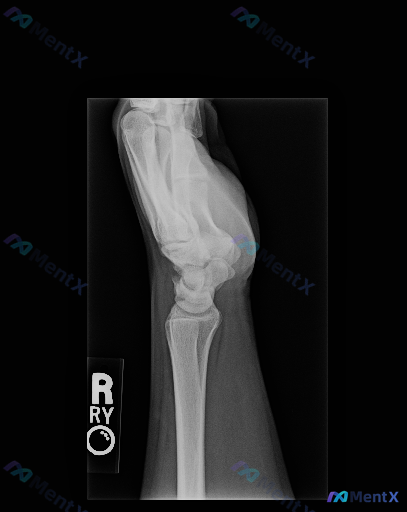

整理到一份右侧腕关节侧位X光片的分析资料,先和大家同步一下客观信息: 影像表现要点: - 骨性结构:桡骨远端、月骨、头状骨纵向轴线基本连续,未见明确脱位或半脱位;侧位下未见明确皮质断裂线或骨折线,各腕骨形态完整,骨皮质边缘清晰 - 骨密度:整体骨密度未见明显异常,骨小梁纹理清晰,无弥漫性疏松或局限性...

整理到一则腕关节侧位X光片的影像观察资料,客观描述如下: - 骨骼方面:桡骨远端背侧、掌侧皮质轮廓清晰,未见明显皮质中断或台阶征;尺骨茎突及可见腕骨皮质连续;未见明显透亮骨折线、皮质裂纹、塌陷或骨小梁紊乱。 - 关节对位:腕骨排列符合生理曲线,未见明显月骨脱位/半脱位;头状骨轴线与桡骨长轴基本对齐;...